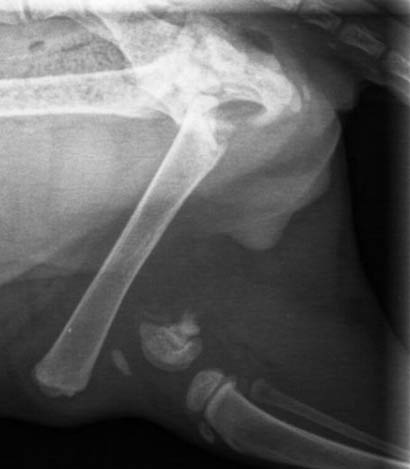

Das kleine Fellbündle wurde gefunden und ins Tierheim gebracht (und leider nicht wieder abgeholt), dort stellte man fest, dass er schreckliche Schmerzen im hinteren Bereich hatte. Um dem hübschen Bub Erleichterung verschaffen zu können, wurde er gleich dem Tierarzt vorgestellt. Leider gab es dort keine guten Neuigkeiten, er hatte sich einen schweren Bruch des Oberschenkels zugezogen, welcher sofort operiert werden musste.